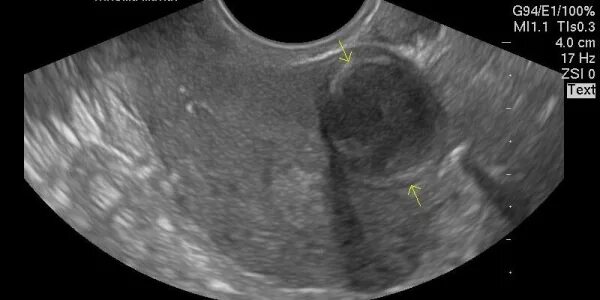

Миома матки и беременность. миома матки реабилитация. миома матки тактика ведения. тактика ведения при миоме матки.Миома матки при беременности. миома матки и беременность. беременность осложненная миомой.Миома приибере енности. шеечная миома матки при беременности. миома матки большого размера и беременность.Миома приибере енности. осложнения беременности при миоме матки. миома матки и беременность. миома матки питание диета.Миома матки и беременность.Диета при фибромиоме матки. миома матки и беременность. что нельзя при миоме матки.Миома матки и беременность. рожать при миоме матки.Можно рожать с миомой маткиМожно рожать с миомой маткиМиоматозные узлы в матке при беременности. миома матки при беременности на ранних сроках. узел в матке при беременности. узлы миомы матки при беременности.Беременность 12 недель и миома матки. миоматозный узел при беременности.Миома матки и беременность.Миома при беременности. показания к миомэктомии. шеечная миома при беременности. миома матки и беременность при миоме.Подслизистая миома матки. подслизистая миома миома матки. симптомы подслизистой миомы матки. осложнения подслизистой миомы матки.Можно рожать с миомой маткиРазмеры узлов при миоме матки. миома матки размер 5.6мм. миома матки недели беременности. миома матки 12 недель размеры.Можно рожать с миомой маткиМожно рожать с миомой маткиПерекрут субсерозного миоматозного узла. перекрут миоматозного узла. перекрут миоматозного узла матки.Размеры миоматозного узла. миома матки множественные миомы матки.Показания к миомэктомии. показания миома матки. показания к хирургическому лечению при миоме матки. лечится ли миома матки.Клинические проявления миомы матки. подходы к лечению миомы матки. миома матки симптомы и признаки.Миома при беременности. миома матки при беременности.Можно рожать с миомой маткиСпособы лечения миомы матки. методы лечения миомы матки больших размеров. миома матки лекарства. как лечить миома матки без операции.Можно рожать с миомой маткиМожно рожать с миомой маткиБез операций миома матки. операция при миоме матки.Миома и беременность на узи. миома матки и беременность узи. миома матки малых размеров на узи.Миома матки при беременности. миомэктомия при беременности.Можно рожать с миомой маткиМожно рожать с миомой маткиМиома матки и беременность. беременность осложненная миомой.Тактика при миоме матки. миома матки тактика ведения.Можно рожать с миомой маткиМожно рожать с миомой маткиУзи беременных. узи матки беременность. миома матки при беременности узи.Можно рожать с миомой маткиМиома матки и беременность.Можно рожать с миомой маткиМожно рожать с миомой маткиМожно рожать с миомой маткиМожно рожать с миомой маткиСубмукозная миома матки узи. миома больших размеров на узи. миома и беременность на узи.Подходы к лечению миомы матки. презентация на тему миома матки. стабильно регрессионное лечение миомы матки. противопоказания при миоме матки.Субмукозная миома матки тип. клинический симптом субмукозной миомы матки:. субмукозный рост миомы матки что это такое. рождающийся субмукозный узел миоматозного узла тела матки.Узловая фибромиома матки. интрамуральная субсерозная миома. узловая интрамуральная миома.Субмукозная миома матки классификация. субмукозная миома матки тип. интрамуральный субмукозный узел.Субмукозная фибромиома матки. субмукозный узел в матке что это.Эмболизация маточных артерий при миоме матки.Лекарства при миоме. миома матки лекарства. миома матки лечение народным средством. миома матки народные средства.Беременность 12 недель и миома матки.Субмукозные миомы матки. интерстициально субмукозная миома матки. рождающийся миоматозный узел на узи. рождающийся субмукозный миоматозный узел.Субсерозная миома и беременность. субсерозная миома лапароскопия. миома матки и беременность.Контрацепция при миоме. лейомиома матки осложнения. миома матки лекарства.Хирургическое лечение миомы матки. показания к миомэктомии. методы диагностики миомы матки.Интрамуральные узлы миомы матки. интерстициально субмукозная миома. интрамурально субмукозная миома матки. субмукозная миома матки тип.Миома по передней стенке матки. миома по передней стенке матки при беременности. большая миома и беременность.Перекрут ножки узла миомы матки. перекрут миоматозного узла матки. миома матки субсерозно-интерстициальный узел. субсерозная миома матки.Эндометриоз шейки матки. субмукозная форма аденомиоза.Можно рожать с миомой маткиМножественная миома матки узи. узи критерии миомы матки. миоматозный узел на узи и беременность.Интрамуральная миома матки что это такое. интрамуральный узел в матке. субмукозно-интрамуральная миома матки.Методы лечения миомы матки больших размеров. способы лечения миомы матки. методы хирургического лечения при миоме матки. радикальные методы лечения.Можно рожать с миомой маткиМожно рожать с миомой матки